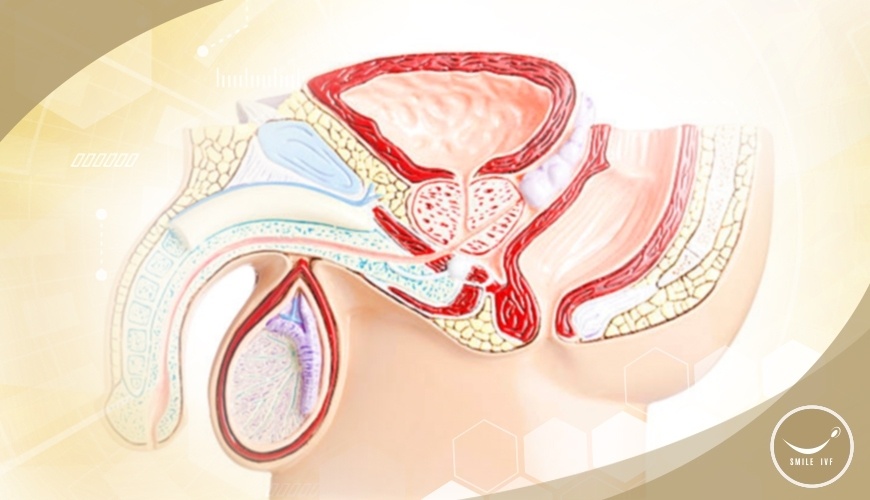

การผ่าตัดหาเชื้ออสุจิ ใช้ในกรณีปัญหามีบุตรยาก เกิดจากฝ่ายชาย เกี่ยวกับการสร้าง หรือหลั่งอสุจิ เช่น เป็นหมัน, มีอัณฑะเหลือข้างเดียว, หลั่งน้ำเชื้อได้ แต่ไม่พบตัวอสุจิ, ไม่สามารถหลั่งน้ำเชื้อได้ เนื่องจากท่อนำอสุจิอุดตัน หรือพิการแต่กำเนิด ทีมผู้เชี่ยวชาญด้านการรักษามีบุตรยาก จะทำการดูดเก็บ หรือผ่าตัดจากชิ้นเนื้อ ของอัณฑะโดยตรง เพื่อหาตัวเชื้ออสุจิ จากท่อน้ำเชื้ออสุจิ หรือลูกอัณฑะ แล้วนำไปใช้ ในกระบวนการปฏิสนธิ (ICSI) ต่อไป

การผ่าตัดหาเชื้ออสุจิ มีหลายชนิด แพทย์จะเป็นผู้วินิจฉัย เลือกประเภท ของการผ่าตัด ตามความเหมาะสม PESA (PERCUTANEOUS EPIDIDYMAL SPERM ASPIRATION)

เป็นวิธีการรักษา โดยทั่วไปหากพบว่าไม่มีอสุจิ ในน้ำเชื้อ แพทย์จะใช้เข็มขนาดเล็ก เจาะผ่านถุงอัณฑะ เข้าสู่ท่อหลัก ที่เก็บเชื้ออสุจิ จากนั้นดูดเอาของเหลวที่ได้ ไปตรวจวิเคราะห์ หาตัวเชื้ออสุจิ และประเมินคุณภาพ ก่อนนำไปใช้ต่อไป

ในกรณีที่ดูดแล้ว ไม่สามารถพบเชื้ออสุจิ ในท่อหลักที่เก็บเชื้ออสุจิ แพทย์จะทำการตัดชิ้นเนื้อ ขนาดเล็กจากอัณฑะ ที่มีหลอดสร้างอสุจิขนาดเล็ก ๆ เพื่อนำไปตรวจหาตัวเชื้ออสุจิ ซึ่งวิธีการนี้ ต้องใช้การทำให้หลับ หรือสลบ อาจมีอาการเจ็บปวดบ้าง ซึ่งโดยส่วนใหญ่ จะหายเจ็บปวดภายใน 3 วัน